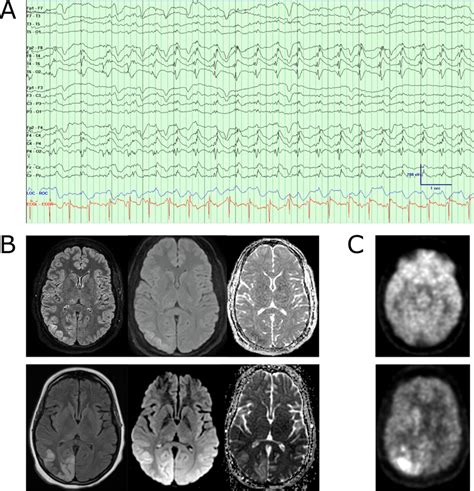

(A) Example of lateralized periodic discharges in the right posterior